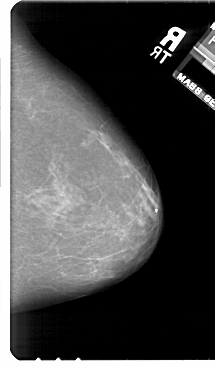

A_1811_1.RIGHT_MLO

RIGHT_MLO LINES 5491 PIXELS_PER_LINE 3226 BITS_PER_PIXEL 12 RESOLUTION 43.5 NON_OVERLAY